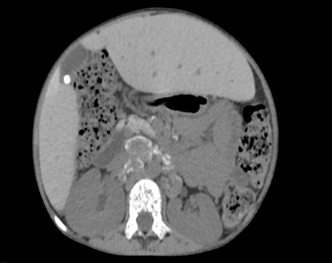

The liver showed

enlargement of the left lobe extending to the left hypochondrium consistent

with a beaver tail variant (right lobe span 12.9 cm), with smooth contours and

no focal lesions. Notably the gallbladder was distended with a 6 mm hyperdense

calculus in the fundus.

Figure 2(a): Non

contrast CT abdomen axial image showing hepatomegaly with left lobe

enlargement, extending to the left hypochondrium (beaver tail variant), 2(b): Non contrast axial

image of the abdomen showing a distended gall bladder containing a 7 mm

hyperdense calculus (arrow)